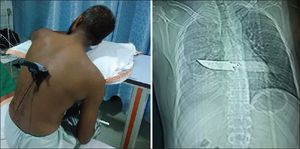

How surgeon managed this case?